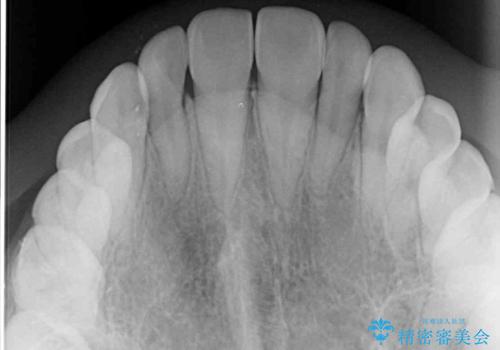

- 前歯のデコボコと、下顎の変位と受け口を気にして来院された患者様です。

初診時には大学病院にて顎の骨を切る外科矯正を勧めましたが、妥協的なゴールでも構わないので外科処置をせずに矯正を行いたいとのことでした。

まずは急速拡大装置にて上顎骨を側方に拡大し、インビザラインにて歯列と咬合を整えることとしました。